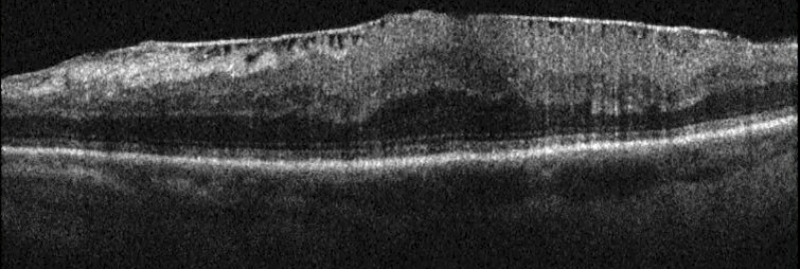

La angiografía fluoresceínica tiene un papel destacado en los pliegues de reciente aparición porque revela el patrón característico de hiperfluorescencia en las crestas combinada con hipofluorescencia en los valles (Figura 1). La tomografía de coherencia óptica (OCT) tiene una especial utilidad en diferenciar los pliegues coroideos de los pliegues retinianos secundarios a patología de la interfase vítreo-retiniana (Figura 2A y Figura 2B)3. Los últimos son más finos, irregulares y menos pigmentados; no se visualizan en la angiografía y la OCT revela su causa (membrana epirretiniana, tracción vítreo-macular…). Recientemente se ha demostrado que los grosores coroideos subfoveales medidos con OCT son mayores en los pacientes con pliegues en comparación con la población normal4. La autofluorescencia es una técnica útil y además no invasiva en la demostración del típico patrón que muestra la angiografía. Se diferencia de ella que el patrón de líneas claras y oscuras aparece de forma inversa (las crestas son hipoautofluorescentes y los valles hiperautofluorescentes)5.

Figura 2A. OCT-SD pliegues retinianos producidos por una membrana epirretiniana.

Figura 2B. OCT pliegues coroideos en el caso de una maculopatía por hipotonía en una cirugía filtrante de glaucoma.